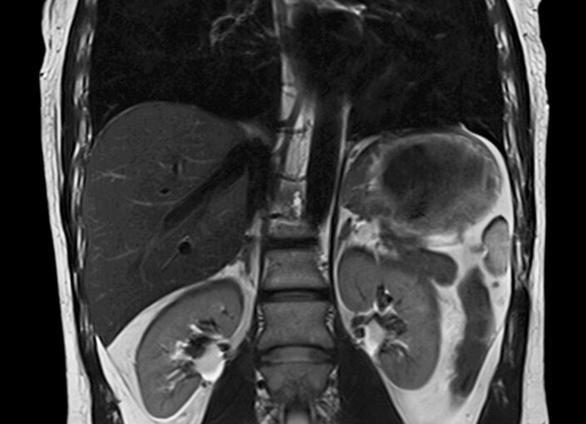

МРТ органов брюшной полости — эффективный метод диагностики, позволяющий контролировать изменения в органах при проведении терапии и в постоперационный период. Исследование МРТ позволяет следить за состоянием исследуемого органа, получать его четкое изображение на глубоких срезах и в разных плоскостях.

На изображении, полученном в ходе исследования, видно клеточные нарушения, повреждения клеточных мембран, определить состояние межклеточного пространства. Также МРТ дает возможность определить верность функционирования клеток того или иного внутреннего органа.

Современный метод диагностики с визуализацией, с помощью которого можно получить детальное изображение и морфологическую картину структур органов и тканей (в том числе брюшной полости) называют магнитно-резонансной томографией (МРТ). Это исследование позволяет выявить структурные изменения органов и тканей, которые невозможно определить с помощью УЗИ или КТ.

Магнитно-резонансная томография помогает определить различные воспалительные процессы, инфекционные заболевания, онкологические образования. Цифровые изображения можно сохранить на компьютере, чтобы более подробно изучить. Рассмотрим, какие органы проверяют на МРТ брюшной полости.

Что показывает МРТ органов брюшной полости

В расшифровке МРТ брюшной полости указывают наличие объёмных образований, их размеры, точную локализацию. Указываются точные размеры паренхиматозных органов (печени, селезёнки, поджелудочной железы, почек), фиксируются дислокации расположения органов. В заключении описывается плотность паренхиматозных тканей, предполагается характер жидкостного содержимого кистозных образований (обычная киста, эхинококковая, абсцесс, гемангиома).